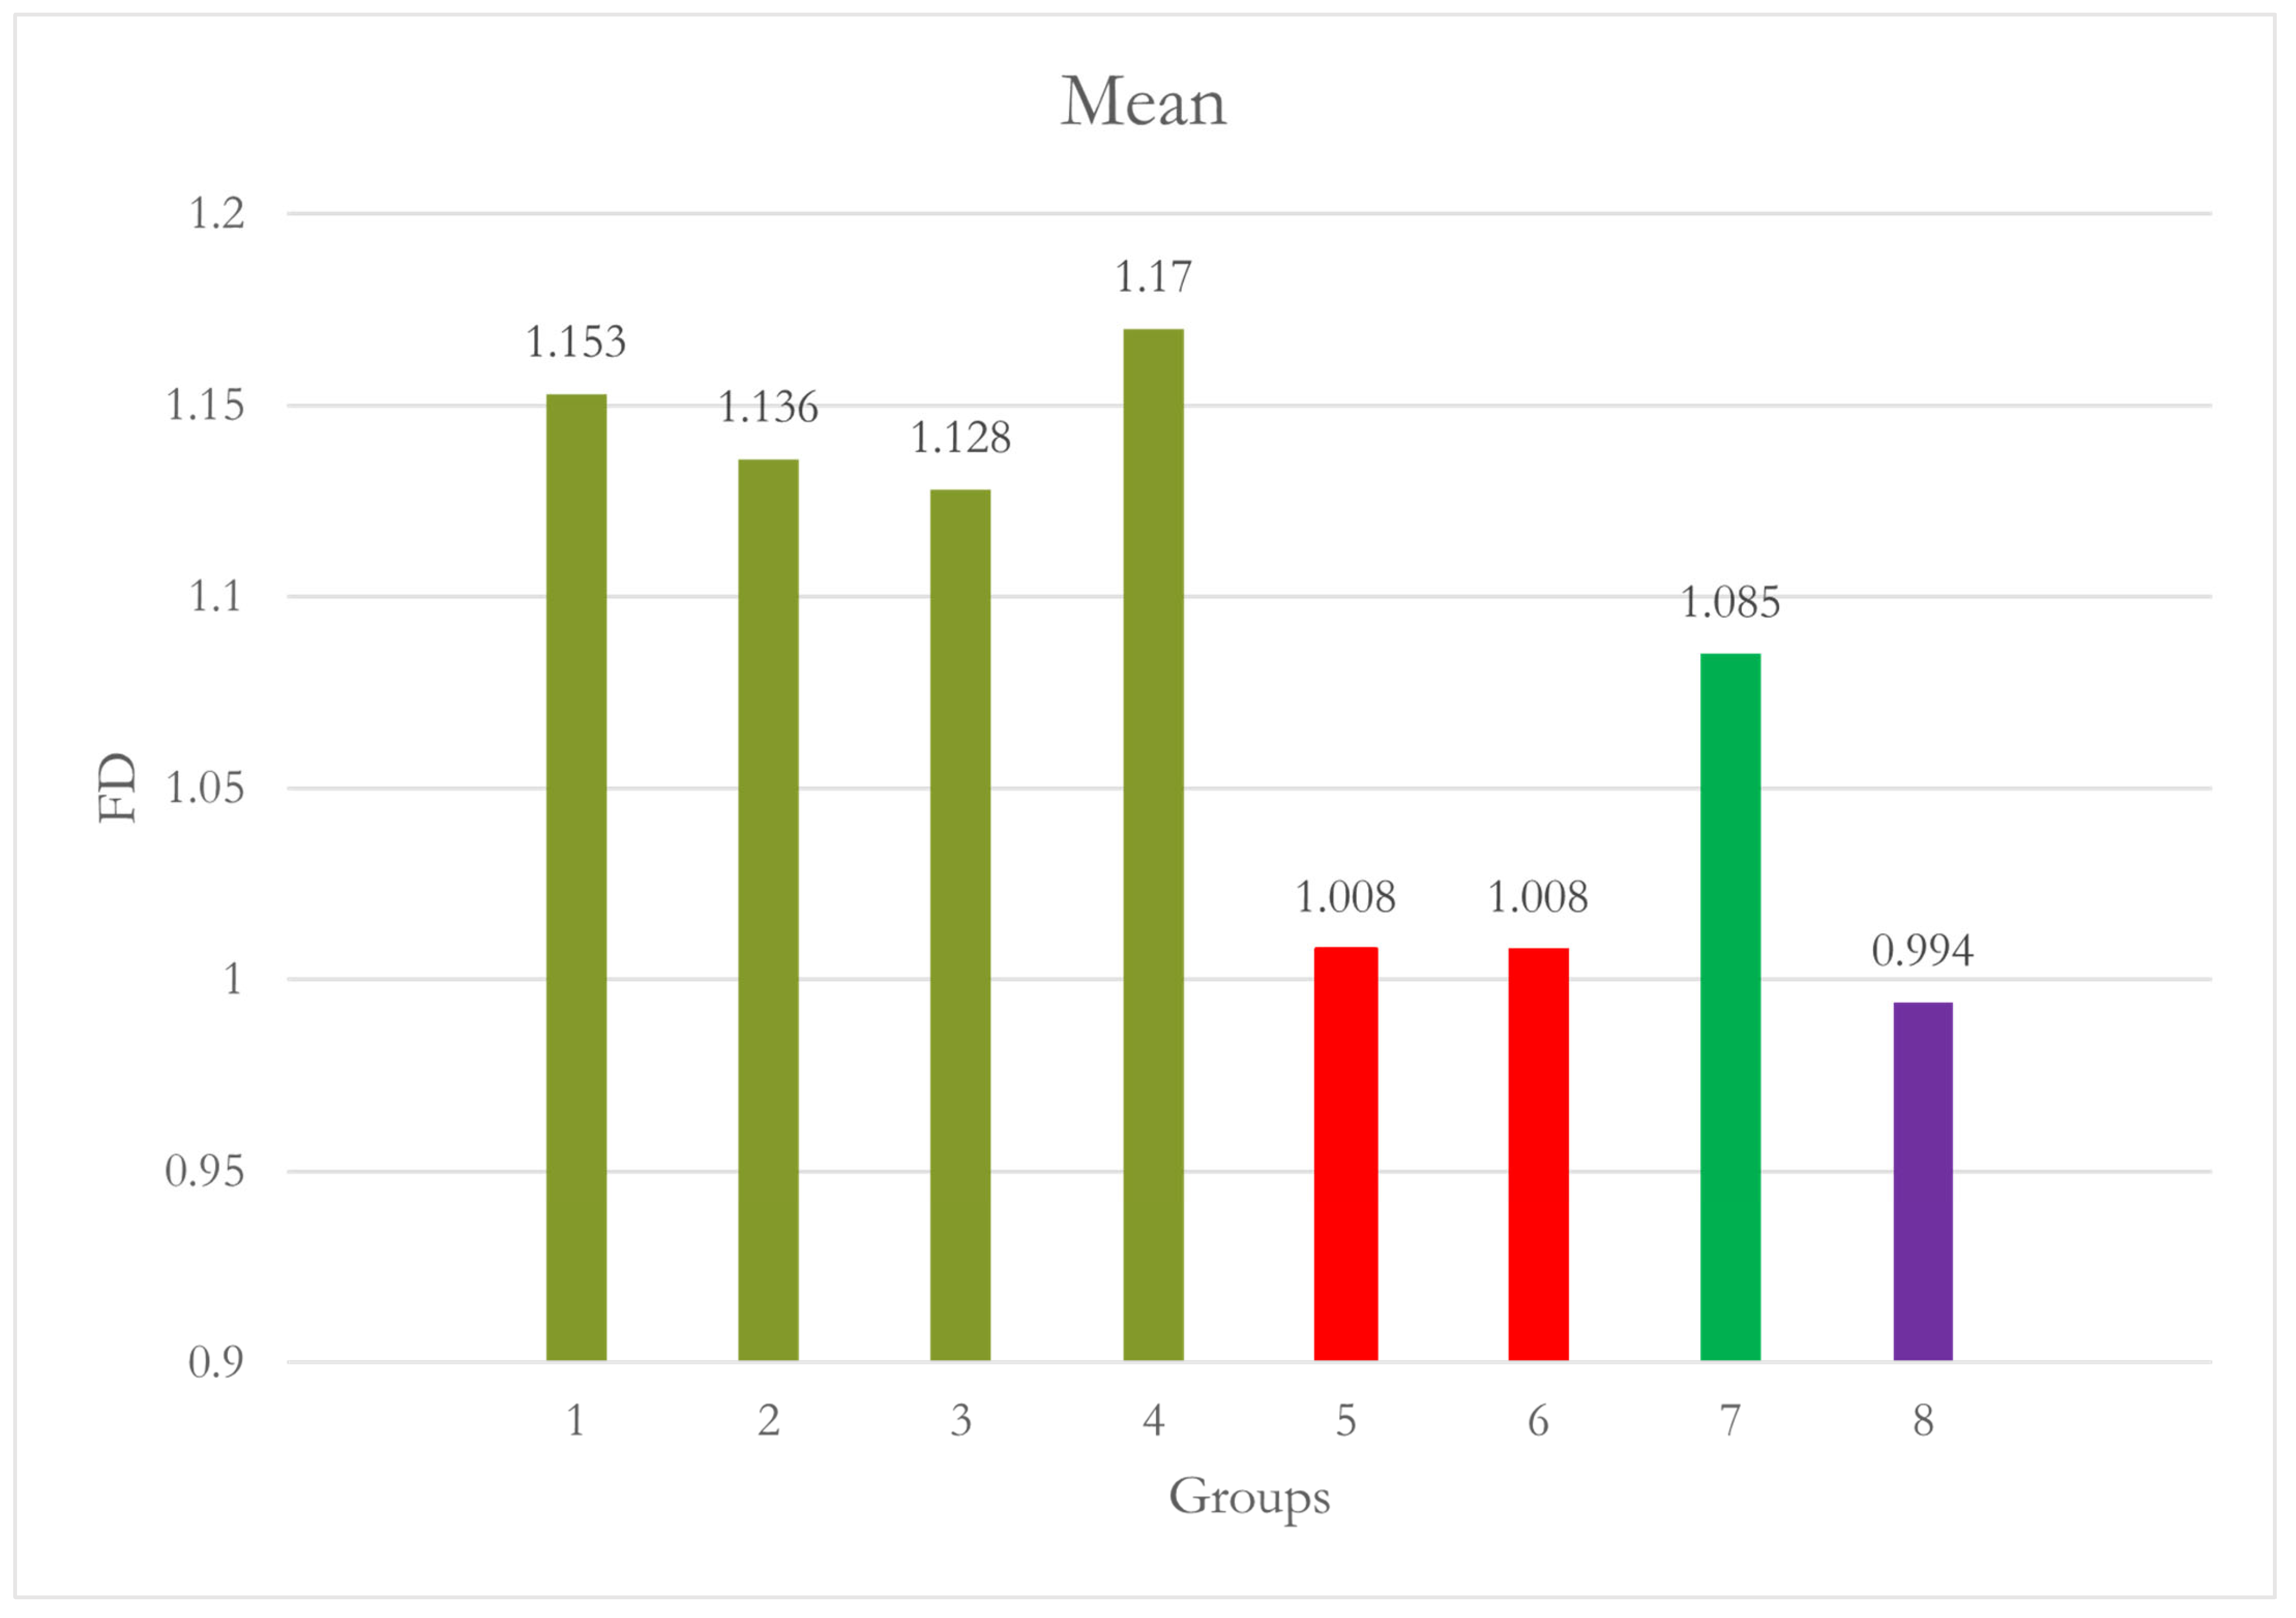

| Site 2 RPM | 1 | 10 | 1.153 | 0.025 | 0.008 | 1.135 | 1.171 | 1.116 | 1.185 | - | 1.000 |

| 2 | 10 | 1.136 | 0.025 | 0.008 | 1.118 | 1.154 | 1.093 | 1.161 | 1.000 | - | |

| 3 | 10 | 1.128 | 0.084 | 0.027 | 1.068 | 1.189 | 0.964 | 1.237 | 0.996 | 1.000 | |

| 4 | 10 | 1.170 | 0.022 | 0.007 | 1.153 | 1.186 | 1.142 | 1.208 | 1.000 | 0.976 | |

| 5 | 10 | 1.008 | 0.077 | 0.024 | 0.953 | 1.063 | 0.845 | 1.136 | 0.002 | 0.009 | |

| 6 | 10 | 1.008 | 0.103 | 0.033 | 0.934 | 1.082 | 0.792 | 1.167 | 0.002 | 0.009 | |

| 7 | 10 | 1.085 | 0.092 | 0.029 | 1.019 | 1.151 | 0.950 | 1.197 | 0.505 | 0.818 | |

| 8 | 10 | 0.994 | 0.115 | 0.036 | 0.912 | 1.077 | 0.823 | 1.199 | <0.001 | 0.002 | |

| Total | 80 | 1.085 | 0.100 | 0.011 | 1.063 | 1.107 | 0.792 | 1.237 | |||